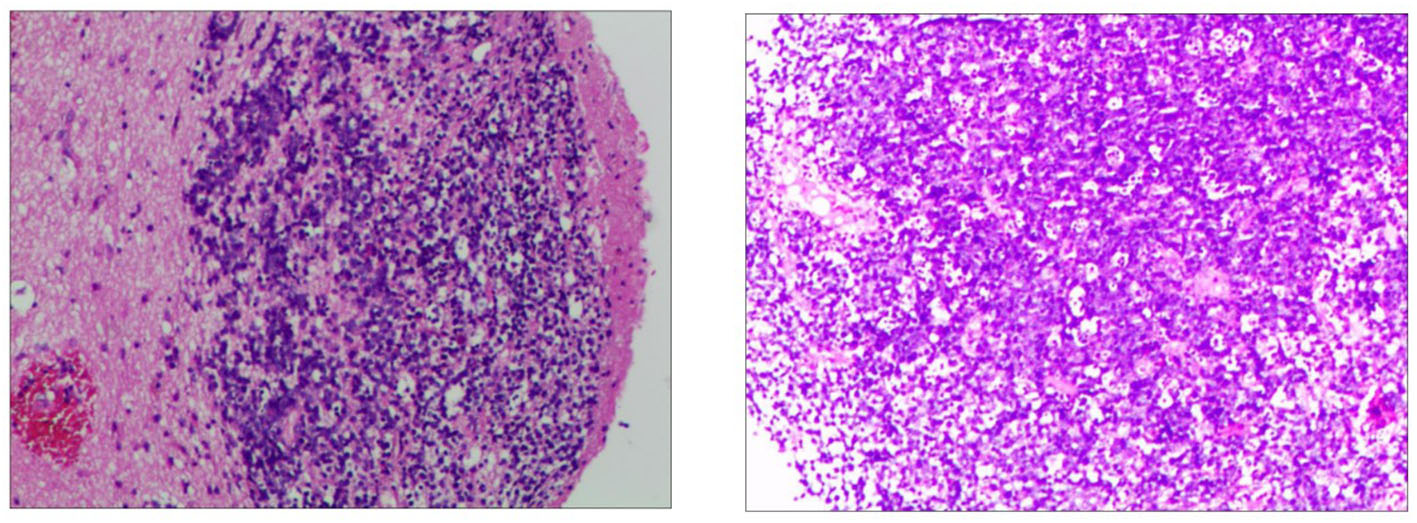

In order to determine the nature of the lesion and ensure smooth cerebrospinal fluid circulation in the third ventricle, the patient underwent a subtotal resection of the third ventricle tumor by transcallosal approach. Analysis of a frozen section was consistent with uncertain PCNSL. Immunohistochemistry revealed the tumor cells were positive for CD10, CD20, Bcl-6, MUM-1, C-MYC(10%), Bcl-2(90%), and Ki-67(80%), and negative for CD3, CD30, cyclin D1, ALK, and EBER in situ hybridization (Figure 3). The P53 was wild-type. Thus, the final diagnosis of the third ventricular tumor was DLBCL with a germinal center subtype. Postoperatively, the patient was in a shallow coma, and in poor overall condition. On day 17, he became critically unwell due to respiratory and circulatory failure and arrhythmia. But the families gave up continued resuscitation and requested to be discharged.

Figure 3

Immunohistochemistry of the third ventricular lesion reveals: CD10 (+), CD20 (+), MUM-1 (+), Bcl-2 (+, 90%), Bcl-6 (+), C-myc (+, 10%), Ki-67 (+, 80%), ALK (–), CD3 (–), CD30 (–), cyclin D1 (–), EBER (–), and P53 (wild-type expression).